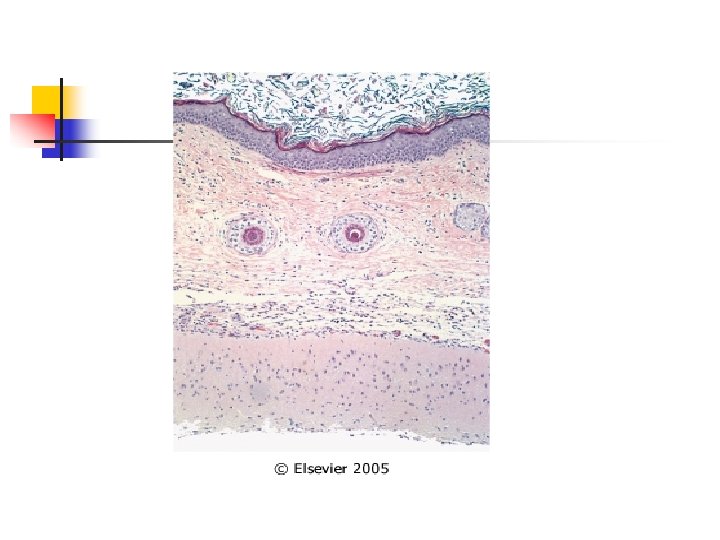

Tumores de células germinales: Teratoma maduro n n Bilateral en 10 a 15% casos Aspecto macro: n n Quistes uniloculares que contienen pelo y material de aspecto sebáceo – queso. En su pared es común encontrar dientes y áreas de calcificación. Aspecto micro: n Pared de epitelio

Tumores de células germinales: Teratoma maduro n Aspecto micro: n n Pared de epitelio escamoso con glándulas sebáceas, pelo y otras estructuras anexiales. Se puede encontrar estructuras de otras capas germinales como cartílago, hueso, tiroides y otros.